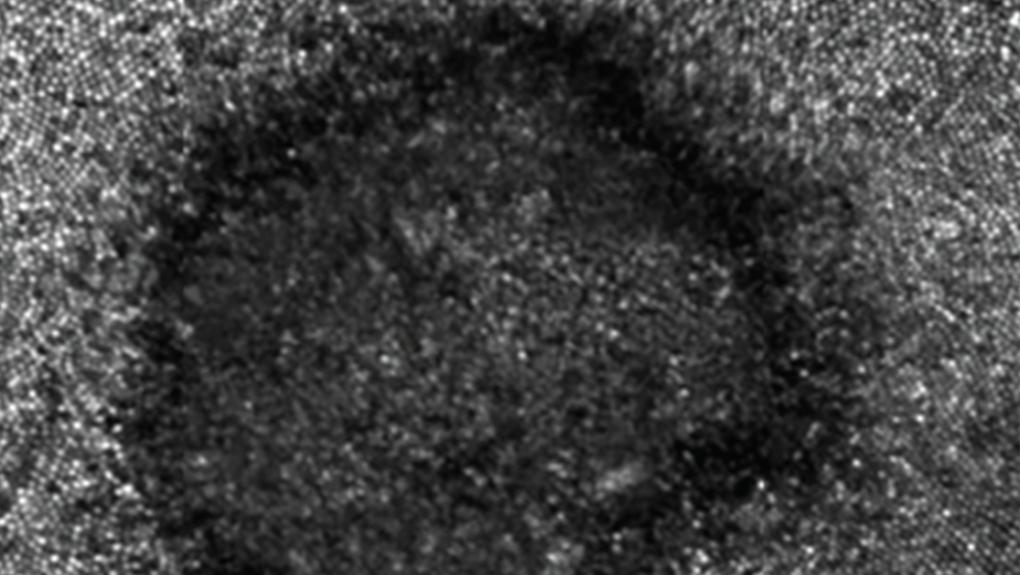

As of April 26, the OAO reported that 118 people have had eye problems after watching the April 8 eclipse. The issues were swelling of the clear layer in front of the eye, eyes not producing enough tears, and damage to the retina from staring at the sun.

Inflammation of the cornea usually gets better within a few days, but looking at the sun can cause permanent vision loss in some cases, according to an OAO spokesperson.